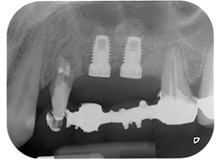

Fig. 1: Paziente di 58 anni. La radiografia preoperatoria mostra una lesione periodontale apicale in corrispondenza del dente 24 e una perdita orizzontale di tessuto osseo alveolare nel secondo quadrante.

Una paziente donna di 58 anni lamentava dolore e aumentata mobilità del dente di appoggio del ponte 24. Era presente infiammazione periodontale con tasche di profondità di 7 mm a livello mesiobuccale e di più di 12 mm a livello distale, nonché coinvolgimento di terzo grado della forcazione. Inoltre, la radiografia rivelava una lesione periodontale estensiva attorno alla regione apicale del dente pretrattato 24 (in altro luogo) a livello endodontico (Fig. 1).

Infine, dopo incisione periostale, il sito è stato chiuso con suturazione passiva con un lembo avanzato a livello coronale, utilizzando materiale assorbile 5-0 da sutura (Fig. 15). La radiografia postoperatoria mostrava entrambi gli impianti nella loro posizione verticale corretta (Fig. 16).

Radiografia postoperatoria

Fig. 16: La radiografia postoperatoria mostra gli impianti in posizione, con il materiale di sostituzione ossea dal rialzo interno mascellare attorno agli apici. Vi è del materiale visibile dalla procedura GTR attorno alle radici del dente 24.